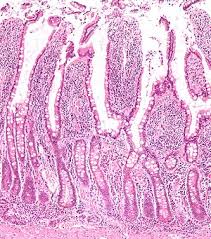

腸管粘膜にある絨毛(じゅうもう)は、有害物質から体を守る「腸管バリア機能」という働きがあります。この絨毛は下剤を使うほど炎症が起きて短くなり、蠕動運動(ぜんどううんどう)ができなくなります。腸の炎症は便秘によって起こりますが、刺激性下剤の乱用によっても悪化します。また「大腸がん」の原因にもなりえます。